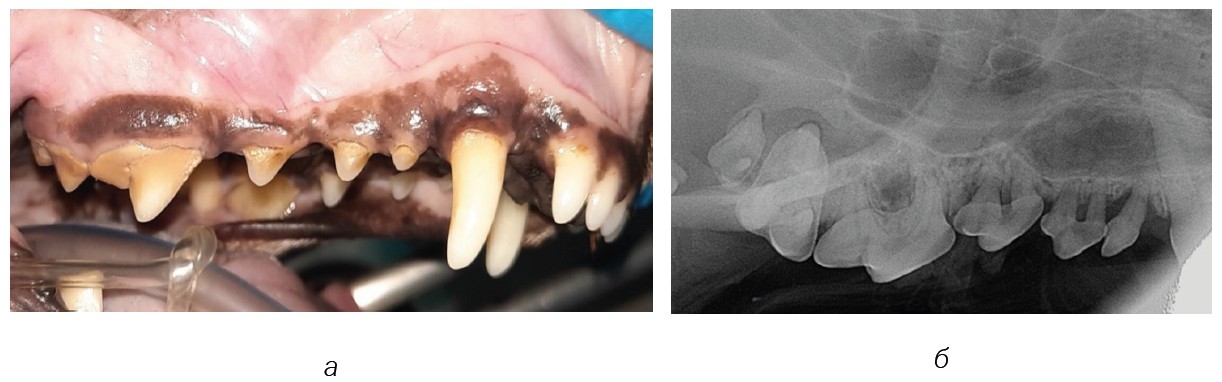

Fig. 8. Dental calculus stage 3: а — quadrant 100; б and в — Intraoral radiograph for stage 3 dental calculus

Source: VTC "Dentalvet".